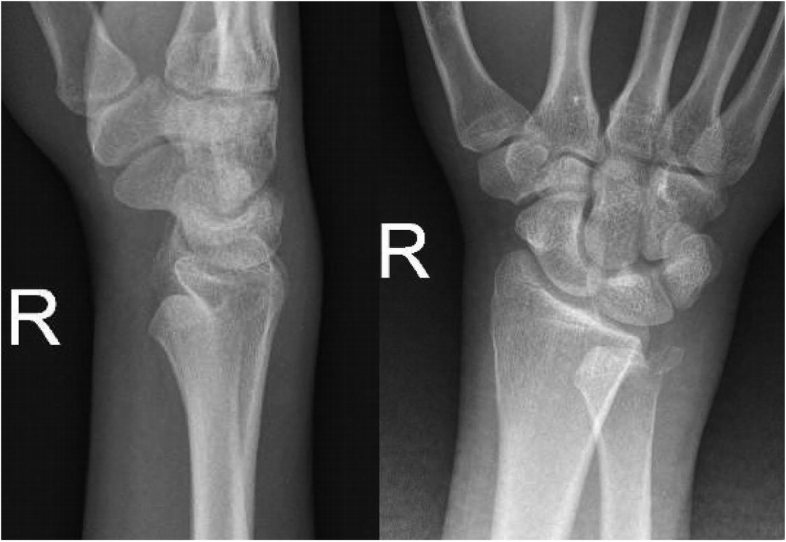

一名19岁男性,右手优势,在用拳头击打墙壁后出现右手腕疼痛和前臂旋转不足。患者以前没有与手腕有关的创伤、医疗或手术史。患者无吸烟及饮酒史,既往无皮质类固醇摄入。体检时,患者的前臂被限制在旋后位置(图1)。尺骨的正常突起背侧缺失,掌侧可触及。皮肤和神经血管状态完好。最初的后前位X线片显示桡骨和尺骨远端重叠并伴有尺骨茎突骨折。侧位X线片显示尺骨掌侧移位与桡骨相关(图2)。

图2. 手腕的X光照片。